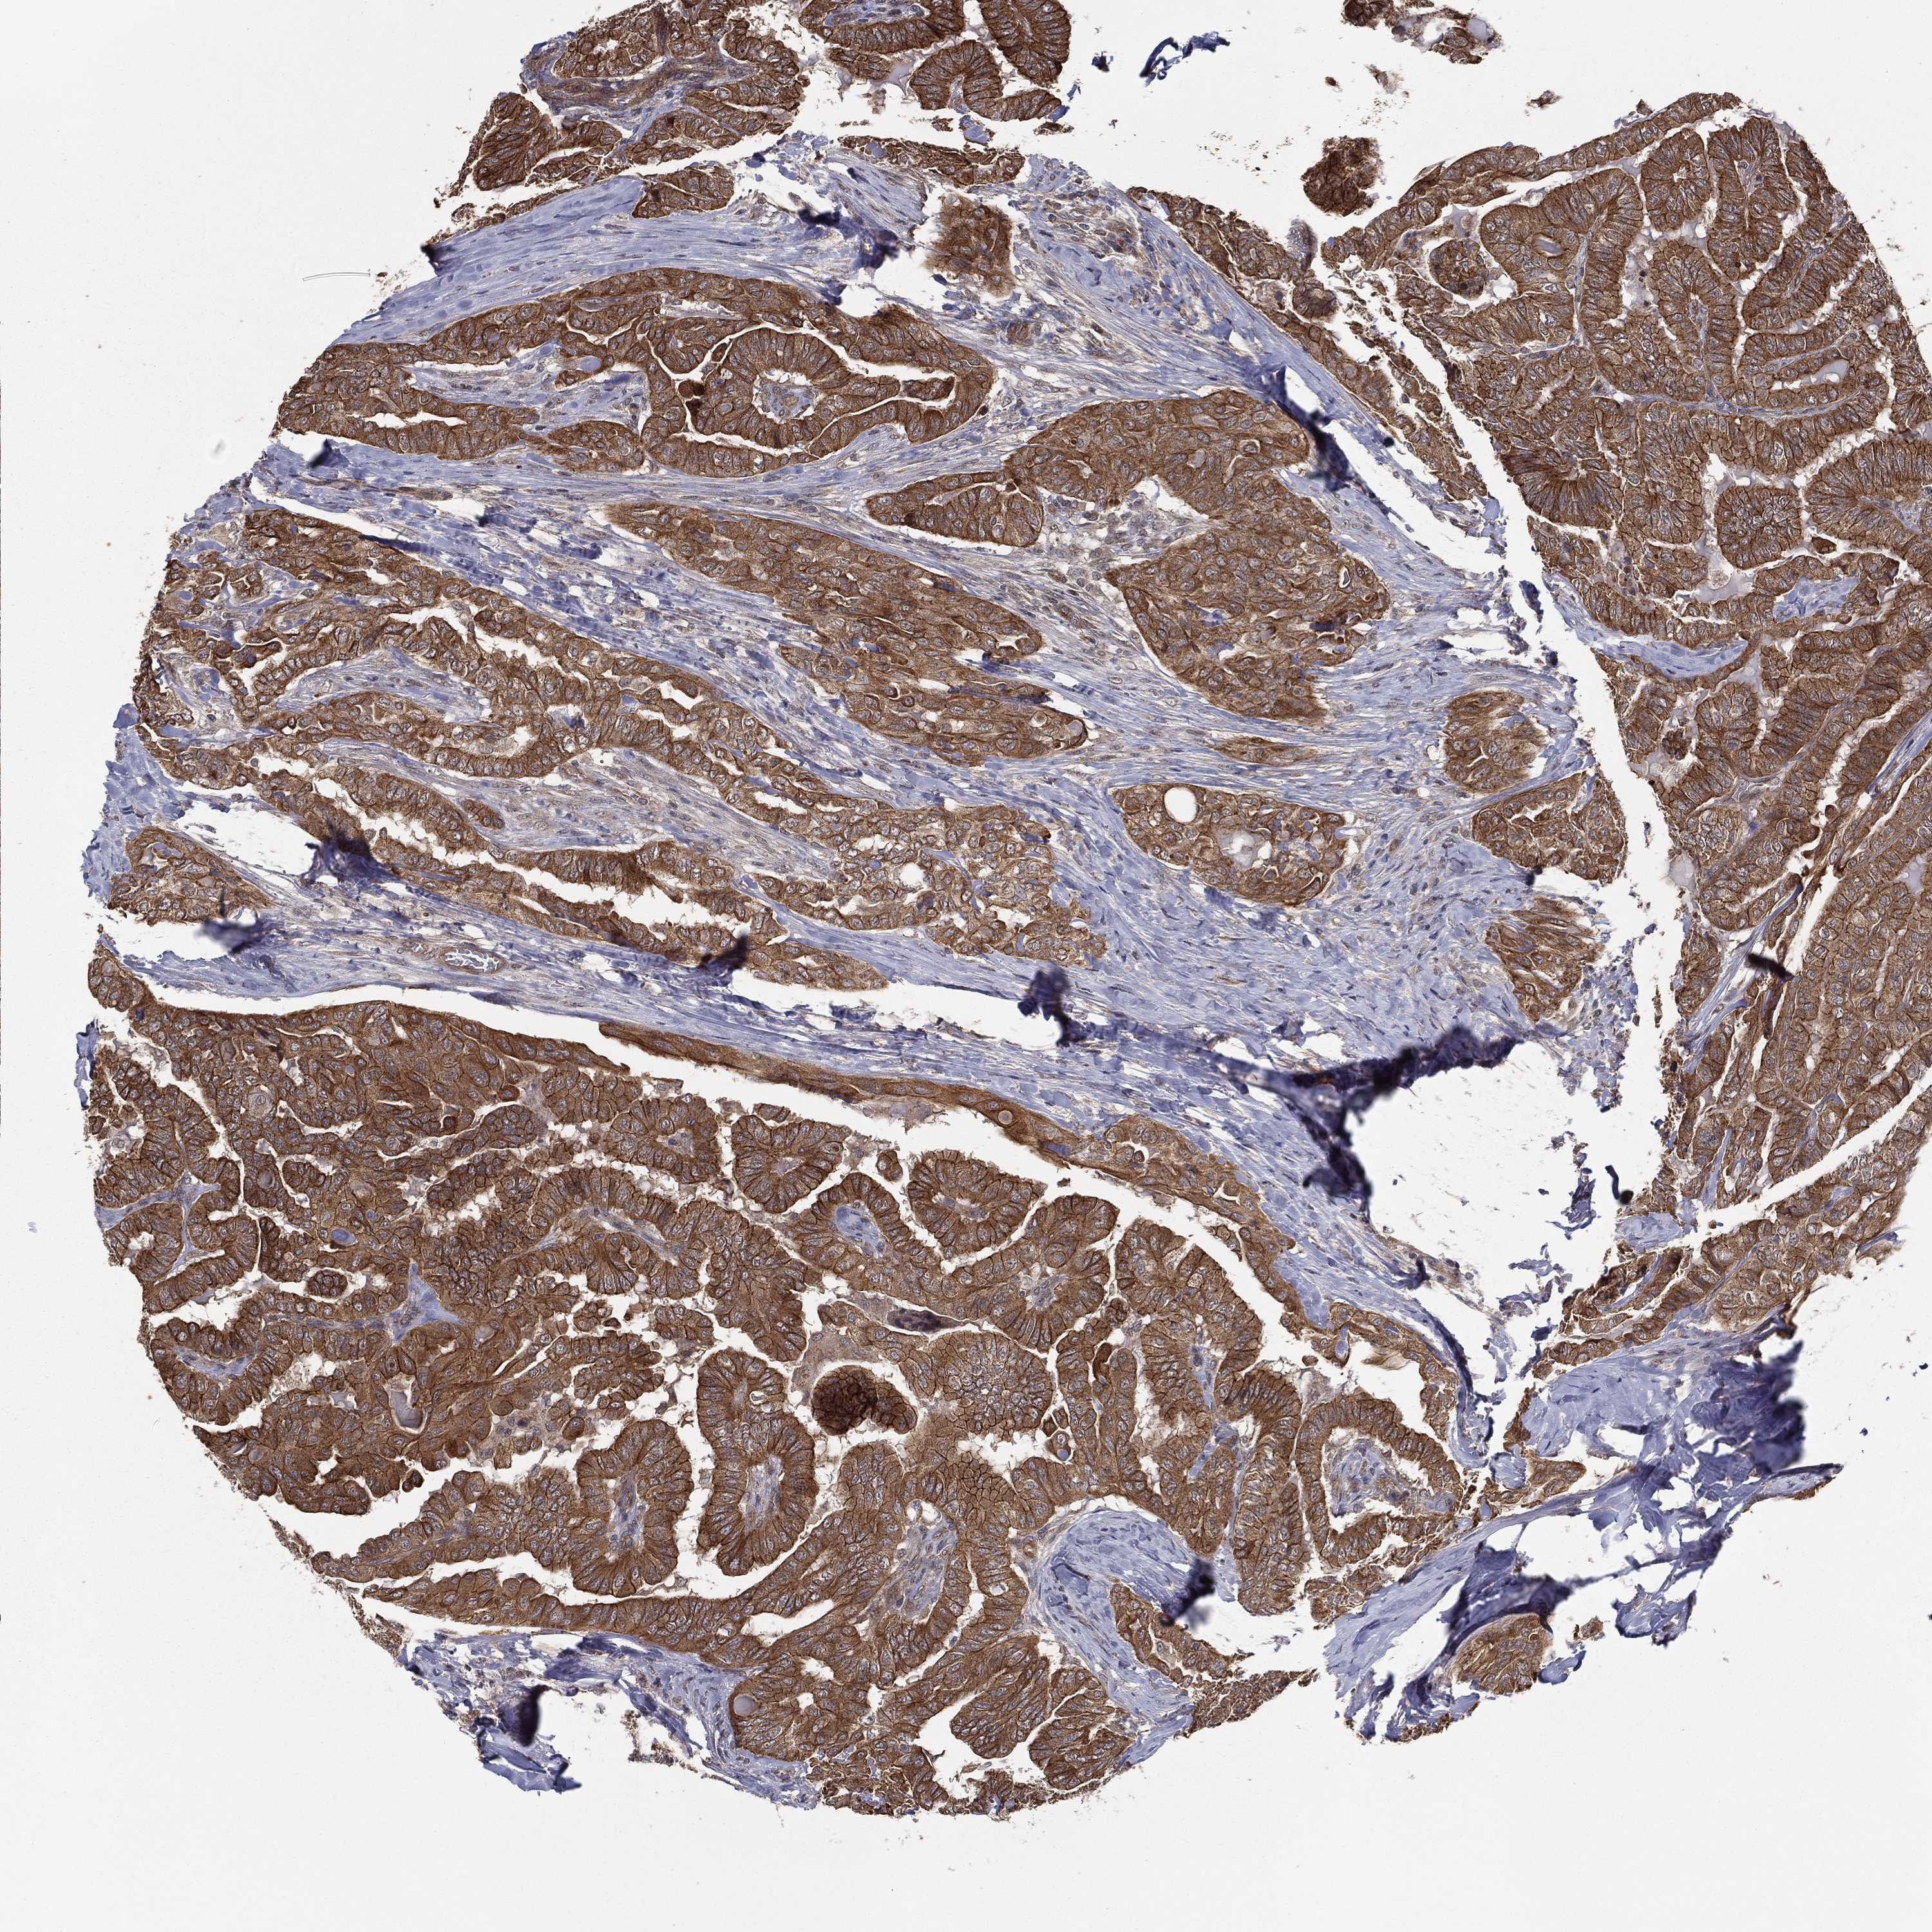

THYROID CANCER - Protein expressioni

A mouse-over function shows sample information and annotation data. Click on an image to view it in a full screen mode. Samples can be filtered based on level of antibody staining by selecting one or several of the following categories: high, medium, low and not detected. The assay and annotation is described here.

Note that samples used for immunohistochemistry by the Human Protein Atlas do not correspond to samples in the TCGA dataset.

Antibody stainingi

Antibody staining in the annotated cell types in the current human tissue is reported as not detected, low, medium, or high, based on conventional immunohistochemistry profiling in selected tissues. This score is based on the combination of the staining intensity and fraction of stained cells.

Each image is clickable and will lead to virtual microscopy that enables deeper exploration of all samples and also displays staining intensity scores, fraction scores and subcellular localization as well as patient and tissue information for each sample.

Antibody HPA041412

Antibody HPA056006

Staining

High

Medium

Low

Not detected

Intensity

Strong

Moderate

Weak

Negative

Quantity

>75%

75%-25%

<25%

None

Location

Nuclear

Cytoplasmic/membranous

Cytoplasmic/membranous,nuclear

Papillary adenocarcinoma, NOS

Follicular adenoma carcinoma, NOS